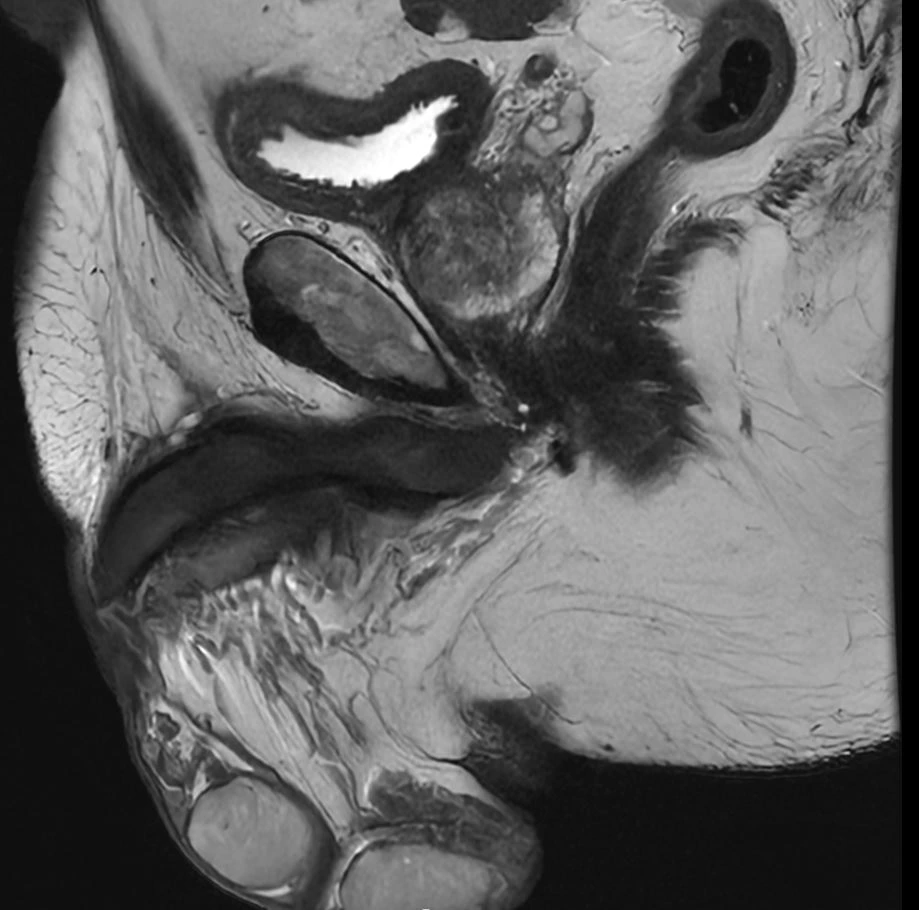

Eksempler på MR-scanninger

- Hos mænd foretages screening af prostata

- Hos kvinder undersøges også livmoder, æggestokke og skede